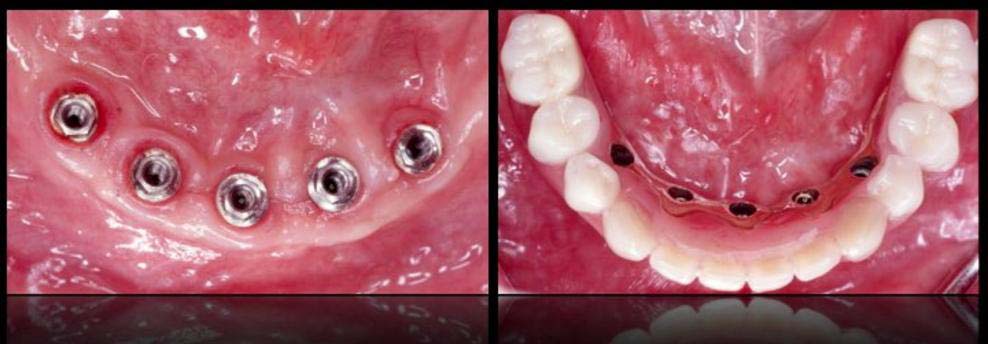

- DENTAL IMPLANTS TO REPLACE MISSING TEETH